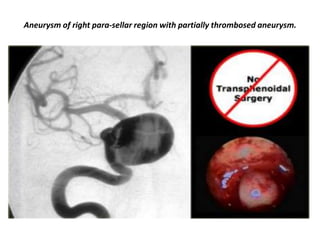

Right para-sellar partially thrombosed aneurysm.

Aneurysm of right para-sellar region with partially thrombosed aneurysm.

Enhanced and non-enhanced study of right para-sellar aneurysm.

The mass is predominantly black and there is a large flow artifact running in the phase-encoding direction.

These findings correspond to rapid blood flow, and the mass must therefore be an aneurysm

Angiogram of the same patient. It demonstrates that the flow in the aneurysm is not laminar,

but that it swirls, gradually filling the lumen with contrast.